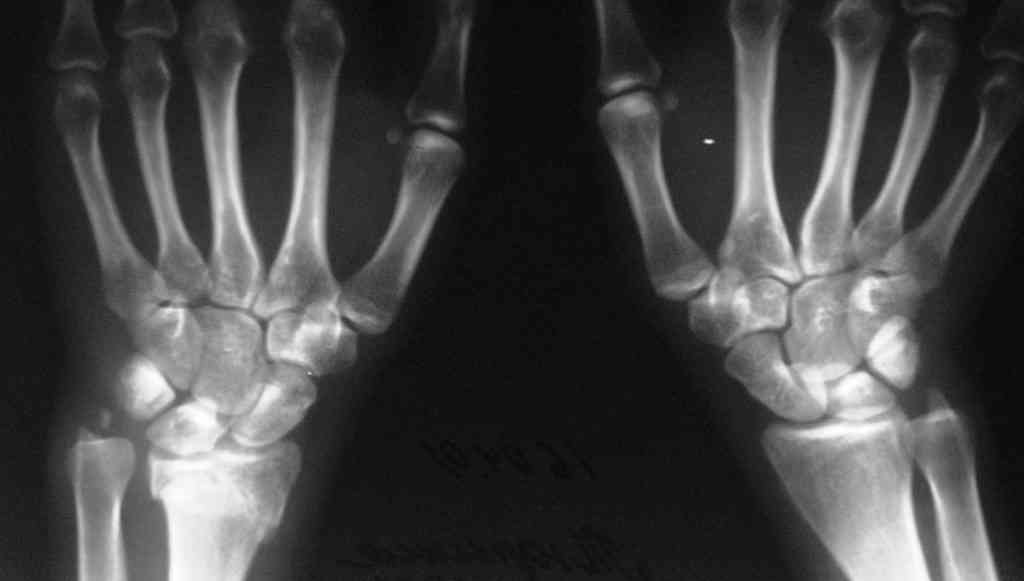

[Ortho] Последствия травмы предплечья

Спице-стержневой   аппарат   с  компактотомией  лучевой  кости,

костная  пластика  локтевой с  удалением  пластины. Не  комфортно,  но

больше  шансов  на  благоприятный  исход. Заканчиваю  лечение  с

похожей  деформацией  лучевой  кости.